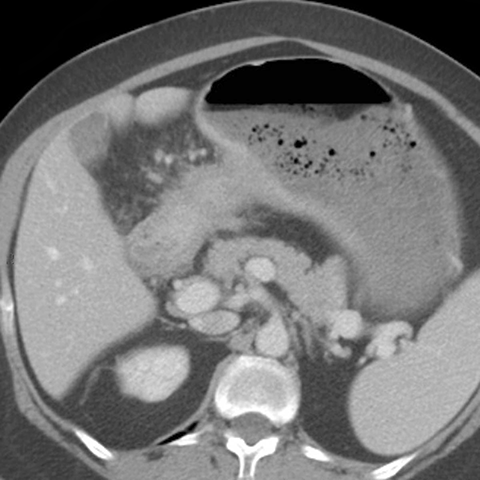

56 year-old male presents with abdominal pain and weight loss [3 of 5]